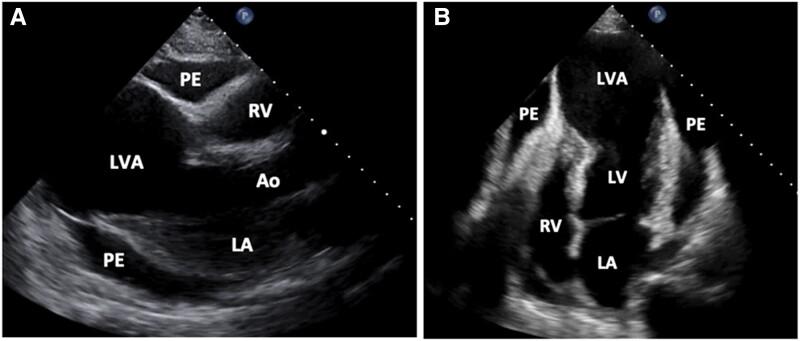

We describe a case of contained rupture of a large left ventricular aneurysm (LVA) presenting with syncope in a 60-year-old male with late presentation myocardial infarction (MI) 6 weeks prior on home triple antithrombotic therapy (TAT). Urgent pericardiocentesis along with imaging techniques including ultrasound, computed tomography angiography (CTA), and cardiac magnetic resonance imaging (MRI) were used for initial diagnosis. Definitive treatment was achieved with excision and repair of the LVA with return to prior functional status 1 month after intervention.